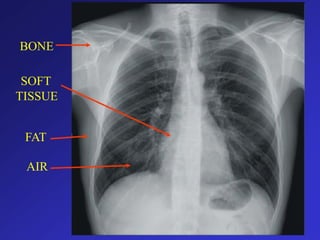

INHERENT CONTRAST

5 Basic Radiographic Densities

• Tissue

–

Air

Fat

Soft Tissues

Bone, Calcium

Metal

• Appearance on XRAY

Black

Dark Gray

Gray

White

Really White

TISSUE

BONE

SOFT